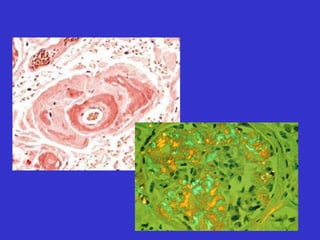

Biopsia y citologia